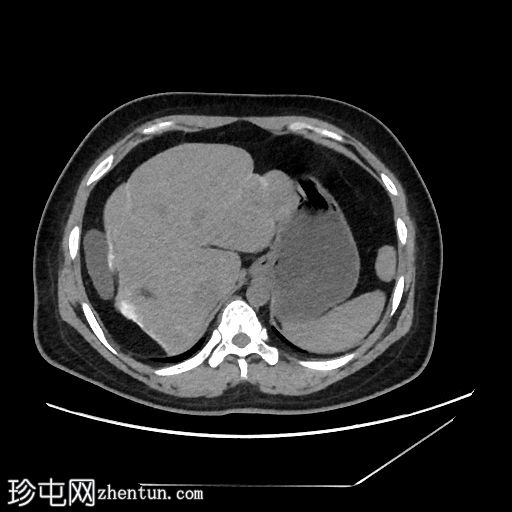

轴位

平扫

线状包膜和实质钙化,呈“龟背样”外观